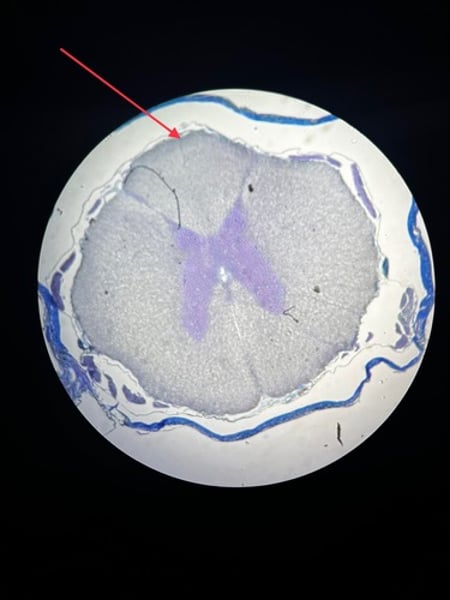

Spinal Cord Slide - anterior gray horn

Spinal Cord Slide - posterior gray horn

Spinal Cord Slide - anterior white column

Spinal Cord Slide - lateral white column

Spinal Cord Slide - posterior white column

Spinal Cord Slide - pia mater

Spinal Cord Slide - dura mater

Spinal Cord Slide - anterior median fissure

Spinal Cord Slide - posterior median sulcus